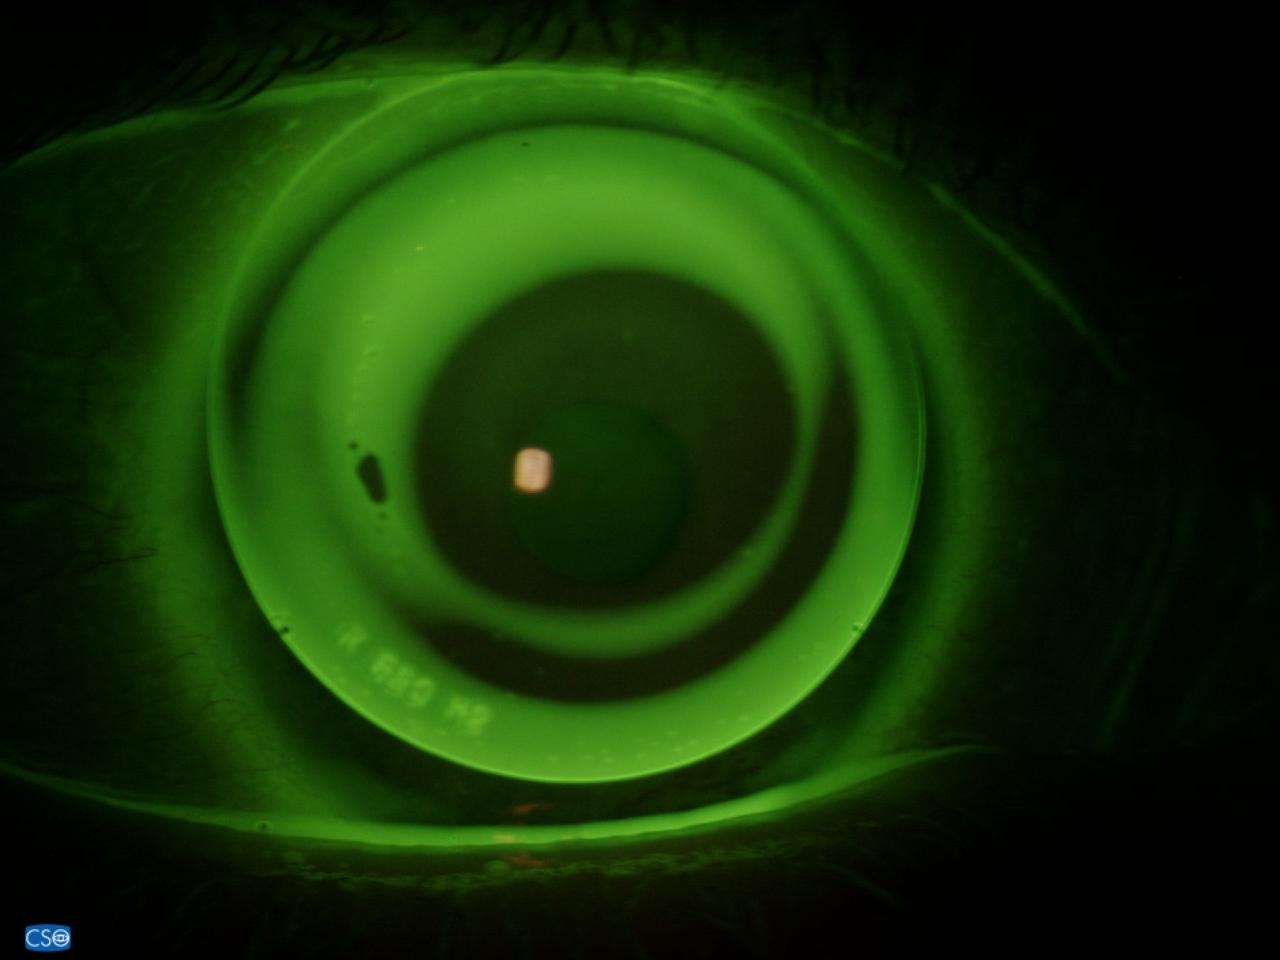

Middenstadium — RGP keratoconuslenzen

Naarmate keratoconus vordert geeft een vormstabiele (RGP) keratoconuslens de beste resultaten. Speciaal voor keratoconus ontwikkelde designs — zoals de Rose K, KBA of McGuire — sluiten nauwer aan op het onregelmatige hoornvlies dan standaard harde lenzen. Het harde optische oppervlak maskeert de kegelform en de ruimte tussen lens en hoornvlies wordt gevuld met traanvloeistof, wat als uniforme corrigerende laag werkt.

Het aanmeten van keratoconuslenzen vraagt om precisie en ervaring. Bij JGK wordt de exacte hoornvliestopografie in kaart gebracht met een corneatopograaf en een OCT-scan (optische coherentietomografie), die de dikte en het verloop van het hoornvlies nauwkeurig vastlegt. Op basis hiervan selecteert onze specialist het meest passende lensdesign.

Omdat de vorm van het hoornvlies bij keratoconus per persoon sterk verschilt — en soms ook per oog — worden lenzen in veel gevallen volledig op maat gemaakt. Na de eerste aanpassing volgen proefperiodes en nacontroles om de pasvorm, centrage en het zicht te optimaliseren. Waar nodig werkt JGK samen met de behandelend oogarts, met name rondom crosslinking-behandelingen of andere chirurgische ingrepen.

Scleralenzen zijn grote harde contactlenzen met een diameter van 14 tot 25 mm die volledig over het hoornvlies heen vallen en rusten op het oogwit (sclera). Doordat ze het hoornvlies niet raken, zijn ze uitermate geschikt bij alle vormen van keratoconus, keratoglobus, pellucid marginal degeneration, na een hoornvliestransplantatie en na laserbehandelingen. JGK beschikt over de meest geavanceerde apparatuur voor individuele aanpassing van scleralenzen en werkt samen met vrijwel alle Europese lensfabrikanten voor maatwerk.